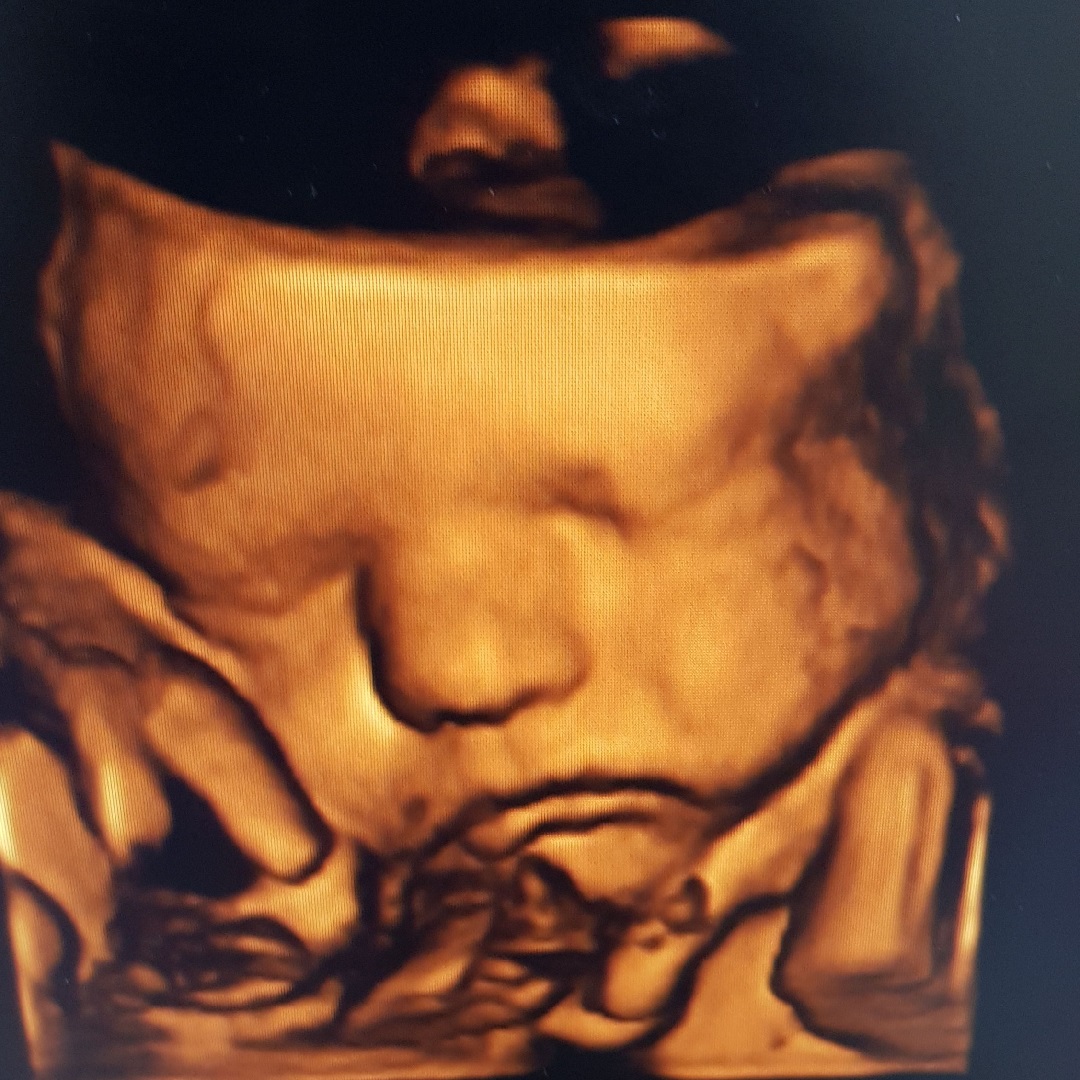

If you’re an expectant mommy, a 3D or 4D Scan can be a touching experience. Contact the helpful sisters at Homegrown Babies at Mopani Crossing Centre on 013 755 5500 for more information.